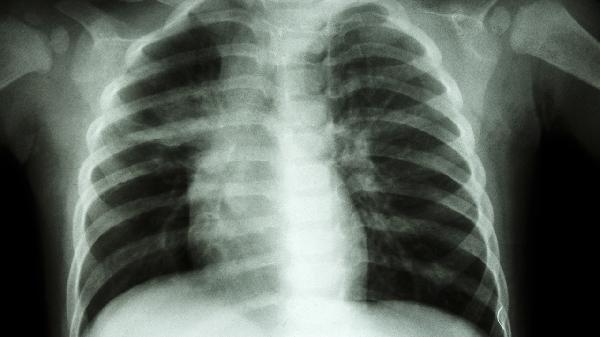

肿瘤或感染造成的胸骨破坏需优先治疗原发病。结核性胸膜炎可能引发胸膜增厚粘连,需规范抗结核治疗;胸壁肿瘤切除后需用钛网重建胸廓。